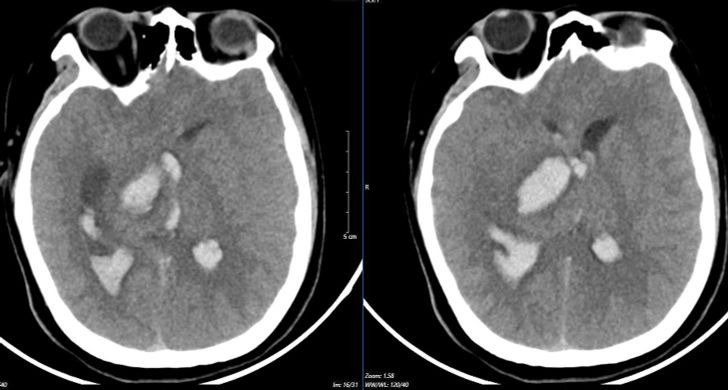

뇌졸중 센터에서 환자의 오른쪽 동공이 확대된 것으로 확인되었습니다. 스캔 결과 뇌동맥류 파열로 인해 뇌에 출혈이 있는 것으로 나타났습니다. 뇌실이 비정상적으로 커지는 합병증이 발생합니다. 체온의 이상 섭씨 39~40도에 달하는 고열이 계속됐다. 뇌혈관 이상은 극도로 위험한 상태였다.